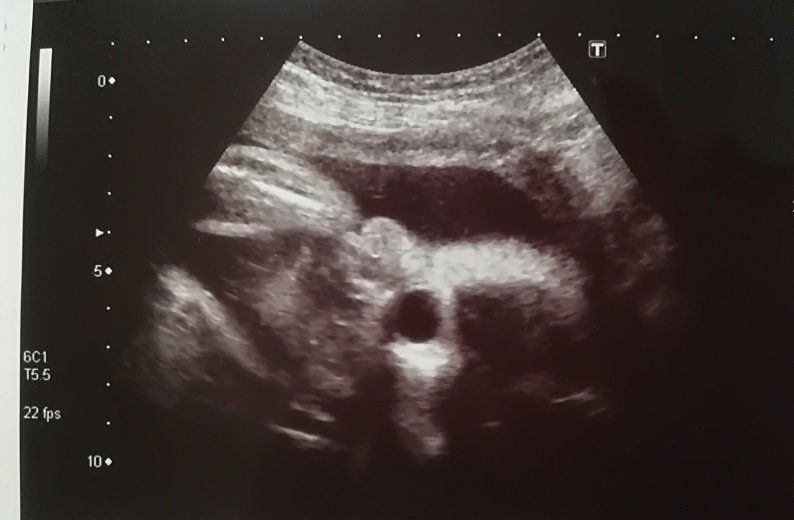

妊娠18週目のエコー写真

頭がくっきり。そして足を曲げている様子もわかります。5カ月目に入り、ようやくつわりがおさまりました。早速、やりたかったマタニティーヨガに挑戦。結果は、お香の匂いと逆転のポーズで吐いてしまいました。ちょっと調子に乗りすぎたようです。でも、ちょうど紅葉の季節にさしかかり、一泊旅行に出かけるなど楽しいことがたくさんできました。